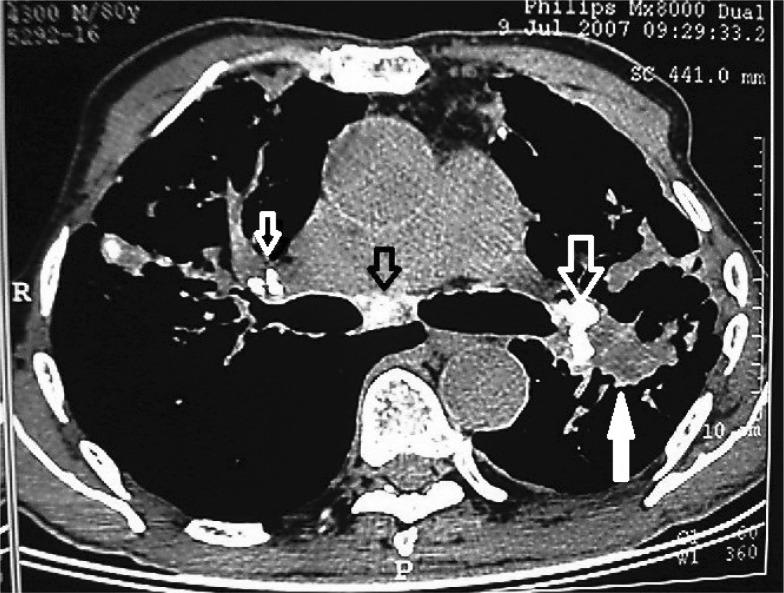

This prospective, case-control study evaluated three groups of 70 patients with a bronchoscopic diagnosis of simple anthracosis and anthracofibrosis and 40 patients with a non-anthracotic diagnosis (control group). Bronchoscopy, chest radiographs and computed tomography (CT) (parenchymal and mediastinal windows) were reviewed. Special attention was given to mass lesions, calcified lymph nodes, bronchi and bronchial stenosis.

Abnormal chest x-rays were observed in 93% of patients with bronchial anthracofibrosis; patchy consolidation was the most prevalent finding. The most significant CT finding was lymph node calcification (80%, odds ratio = 22.9), followed by bronchial calcification and bronchial stenosis (odds ratio = 6 and 2.91, respectively). Other significant findings were mass-like lesions (14%) and collapse (20%). CT findings were unremarkable in less than 1/6 of subjects.

Lymph node and bronchial calcification can serve as accurate signs in diagnosing anthracosis of the lung. In addition, mass lesions, collapse and infiltration may be associated with a benign course.